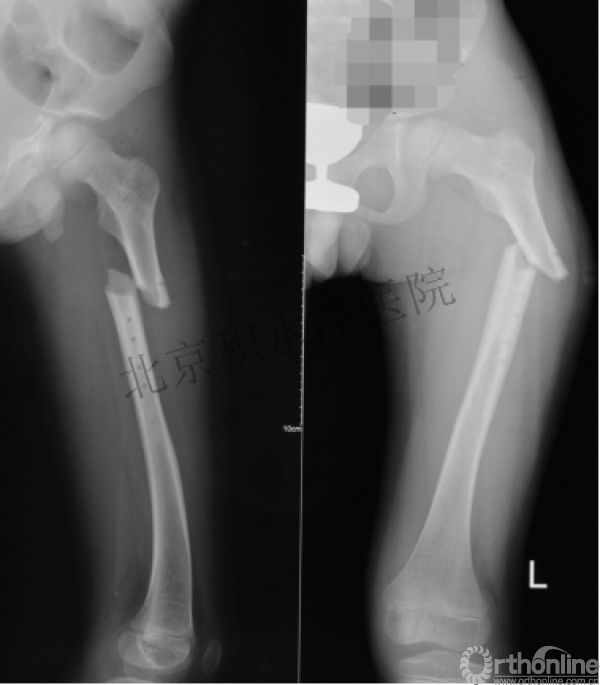

病例分享二

2岁、股骨干骨折,切开+内固定

简单牵引即可!为什么要如此大动干戈?